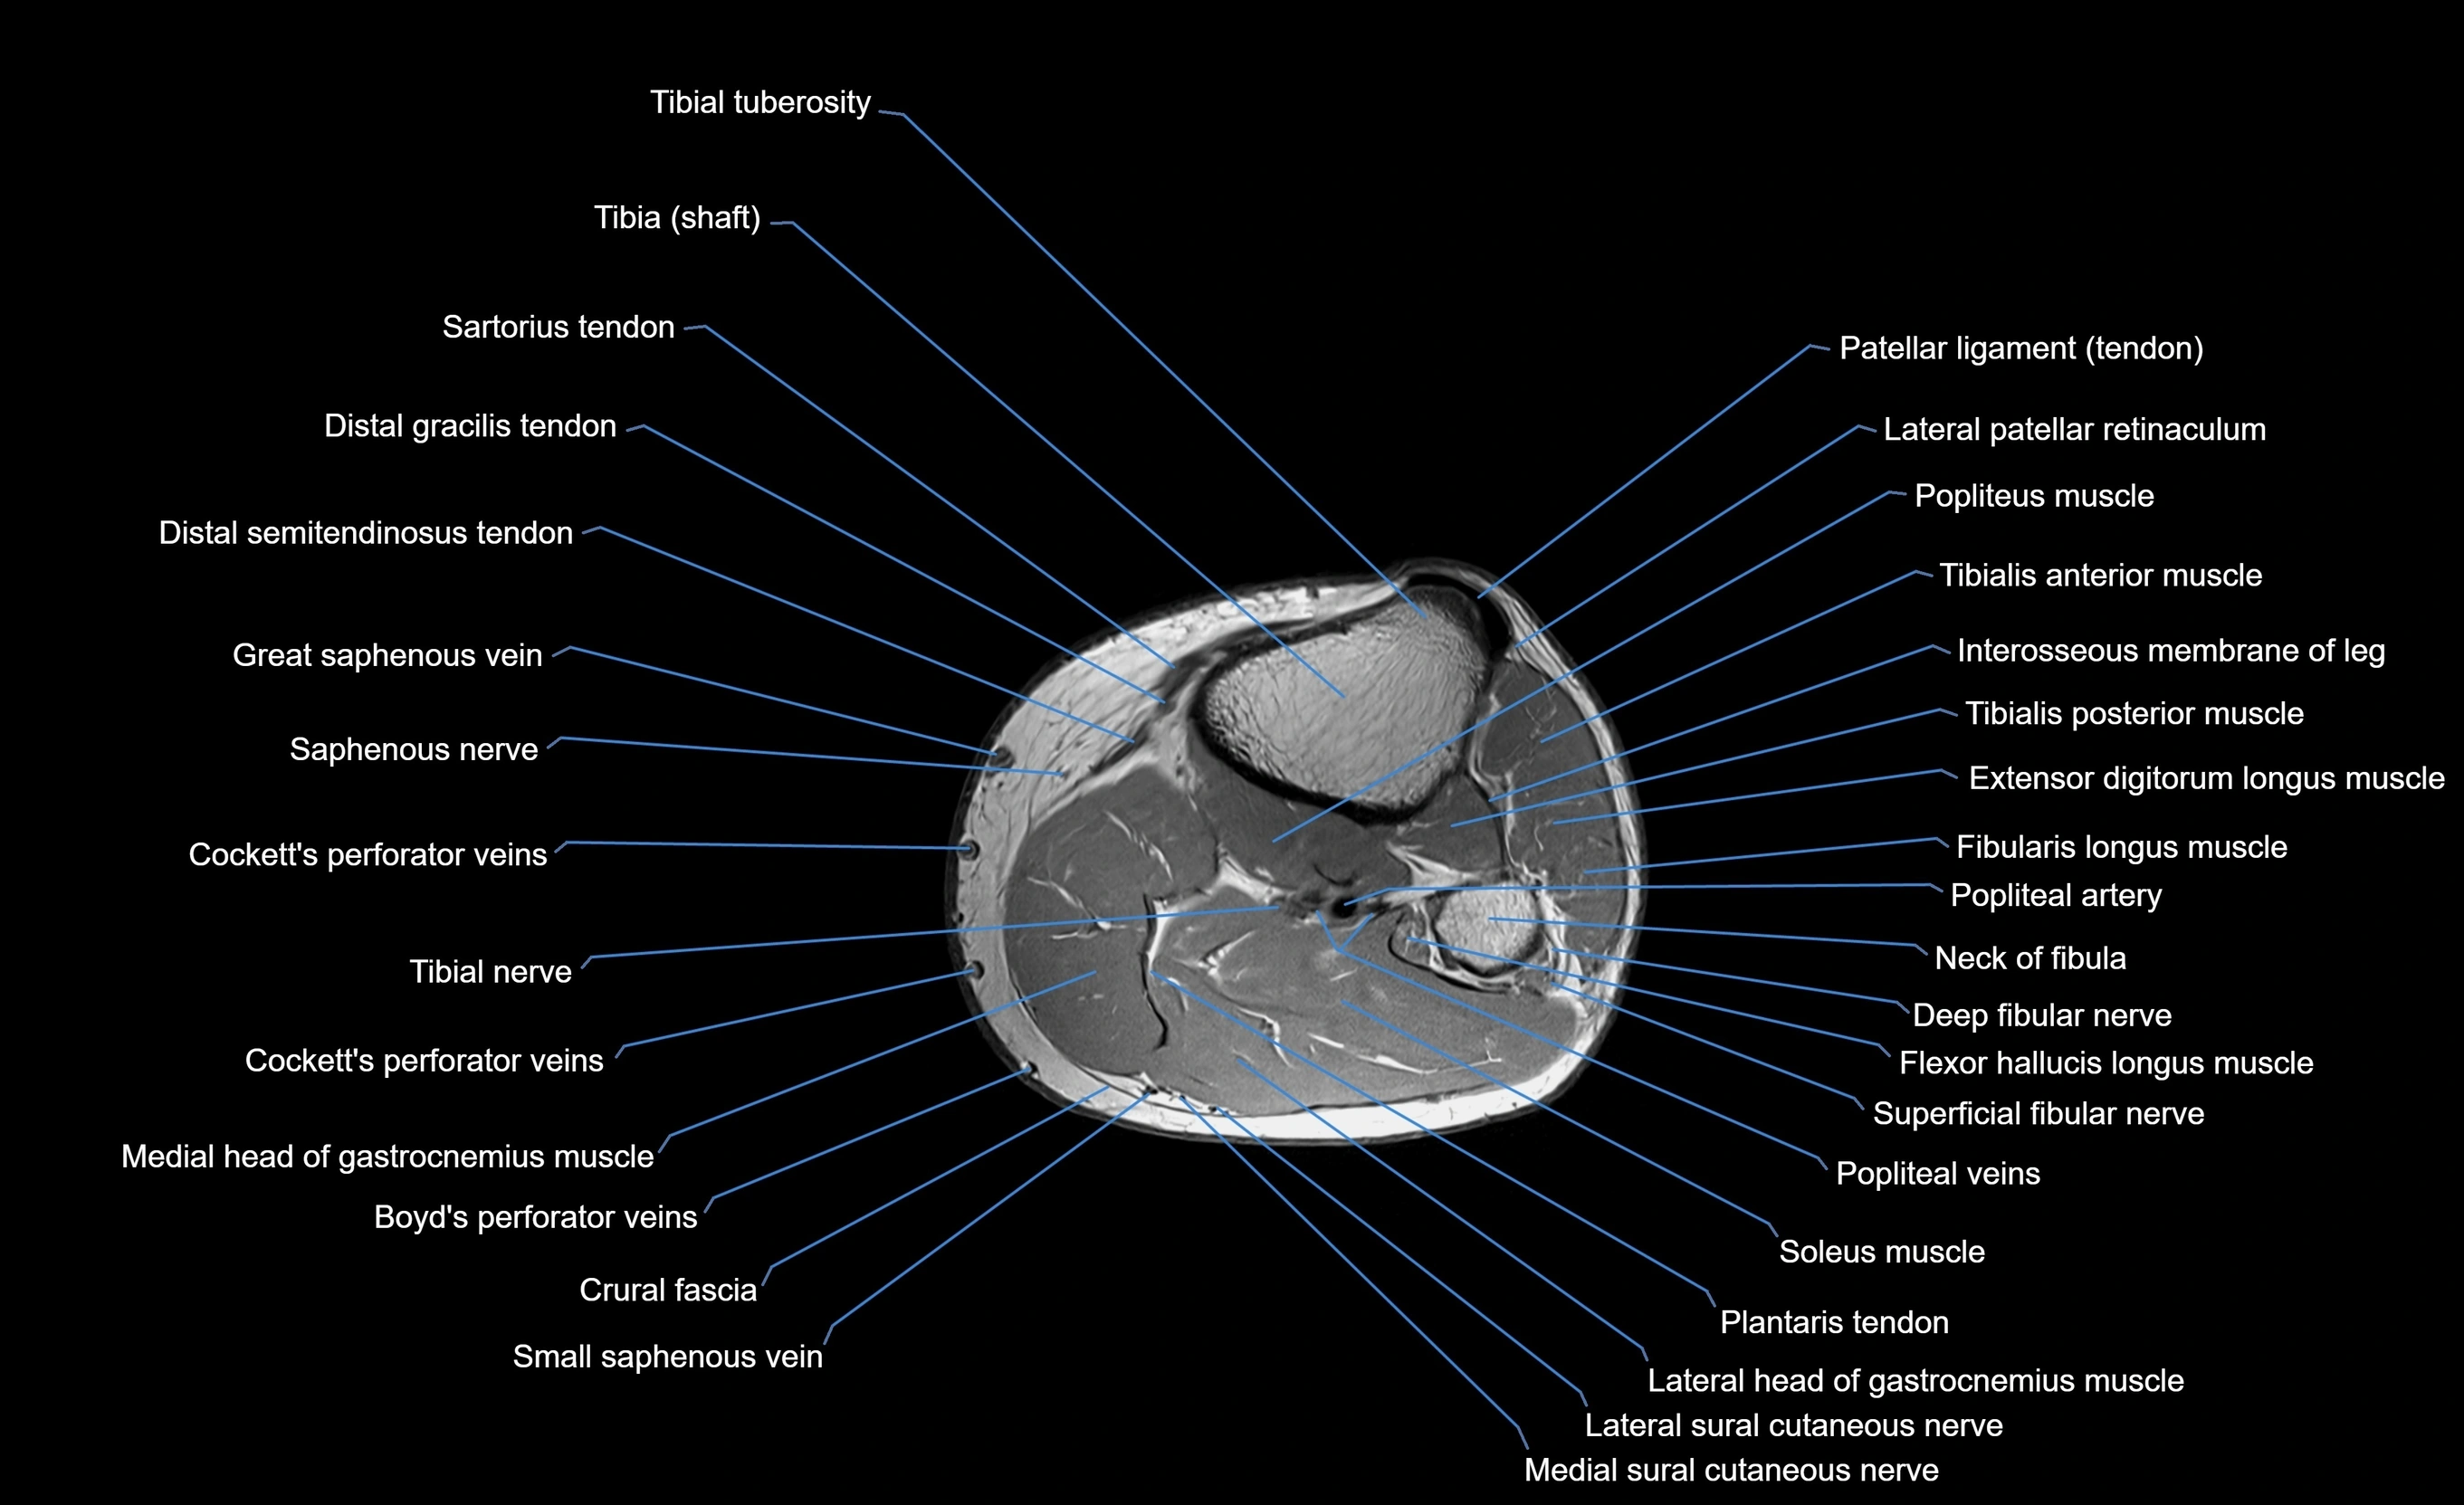

MRI image